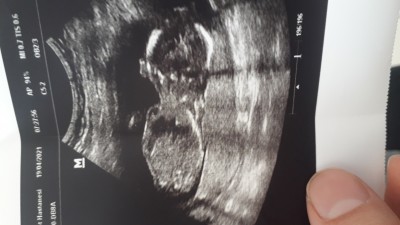

17 haftadayım doktora gittim devlete cinsiyet öğrenemedim doktorum çok umursamaz ulaşım probleminden başka doktora gidemiyorum nefret ettim doktordan ya birkere ağzından bebegin gayet sağlıklı diye bir şey duymadım kalp atışını duymasam iyi diye inanmam ya konuşmak ne kadar zor anlamıyorum bisey sormaya cekiniyorum inanın bende sağlıkçı eşiyim böyle bisey görmedim  cinaiyet için gittim kıza benziyor dedi ama böyle kapıyı açtı tam çıkarken bunu söylüyor ama makine yeterli değil net değil ancak 20 24 de detayli da öğrenirsin dedi gel tekrar bakarız değil 1 ay sonra gel diyor o kadar üzüldüm ki bu davranışlara çok tuhaf

Gebelik haftası 17

Rabbim iyi insanlar    ile karşılaştırısin..  ama  bu ultrasonda  bebegin    cinsel   organı   görünmüyor  ki    hayırlı  evlât  olsun

Sonuçta o bir doktor ve onun görevi seni bilgilendirmek gittiğin hastanede başka kadın doğum doktoru varsa onunla devam et derim cinsiyet konusunda da galiba bebeğin arkası dönük ultrason kalitesi de evet biraz kötü o yüzden bişey diyemiyorum doktorunu degistir bence